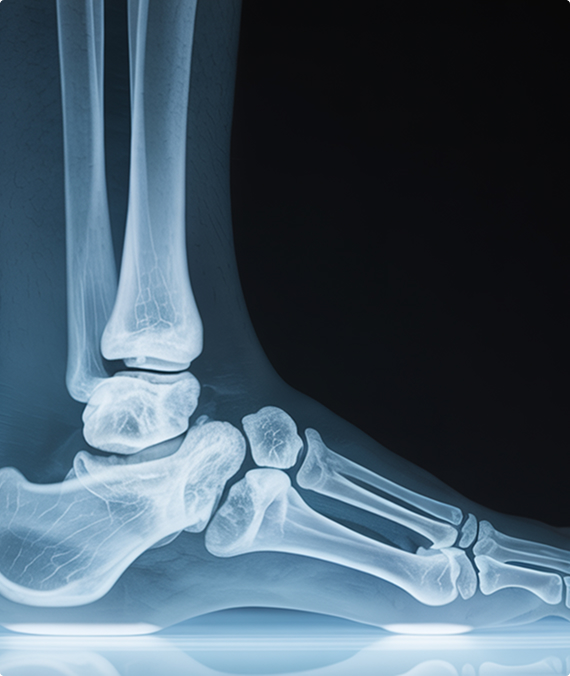

A stress fracture isn’t a full break—it’s a microscopic crack in the bone that comes from repetitive force. But don’t let the “micro” fool you: left untreated, a stress fracture can sideline you for months or lead to a full-blown fracture that does require surgery.

Most stress fractures in the ankle and foot are caused by overuse, improper biomechanics, low bone density, or a sudden increase in activity. If you’re active, on your feet a lot, or over 40 and not bouncing back like you used to—this is a real risk.